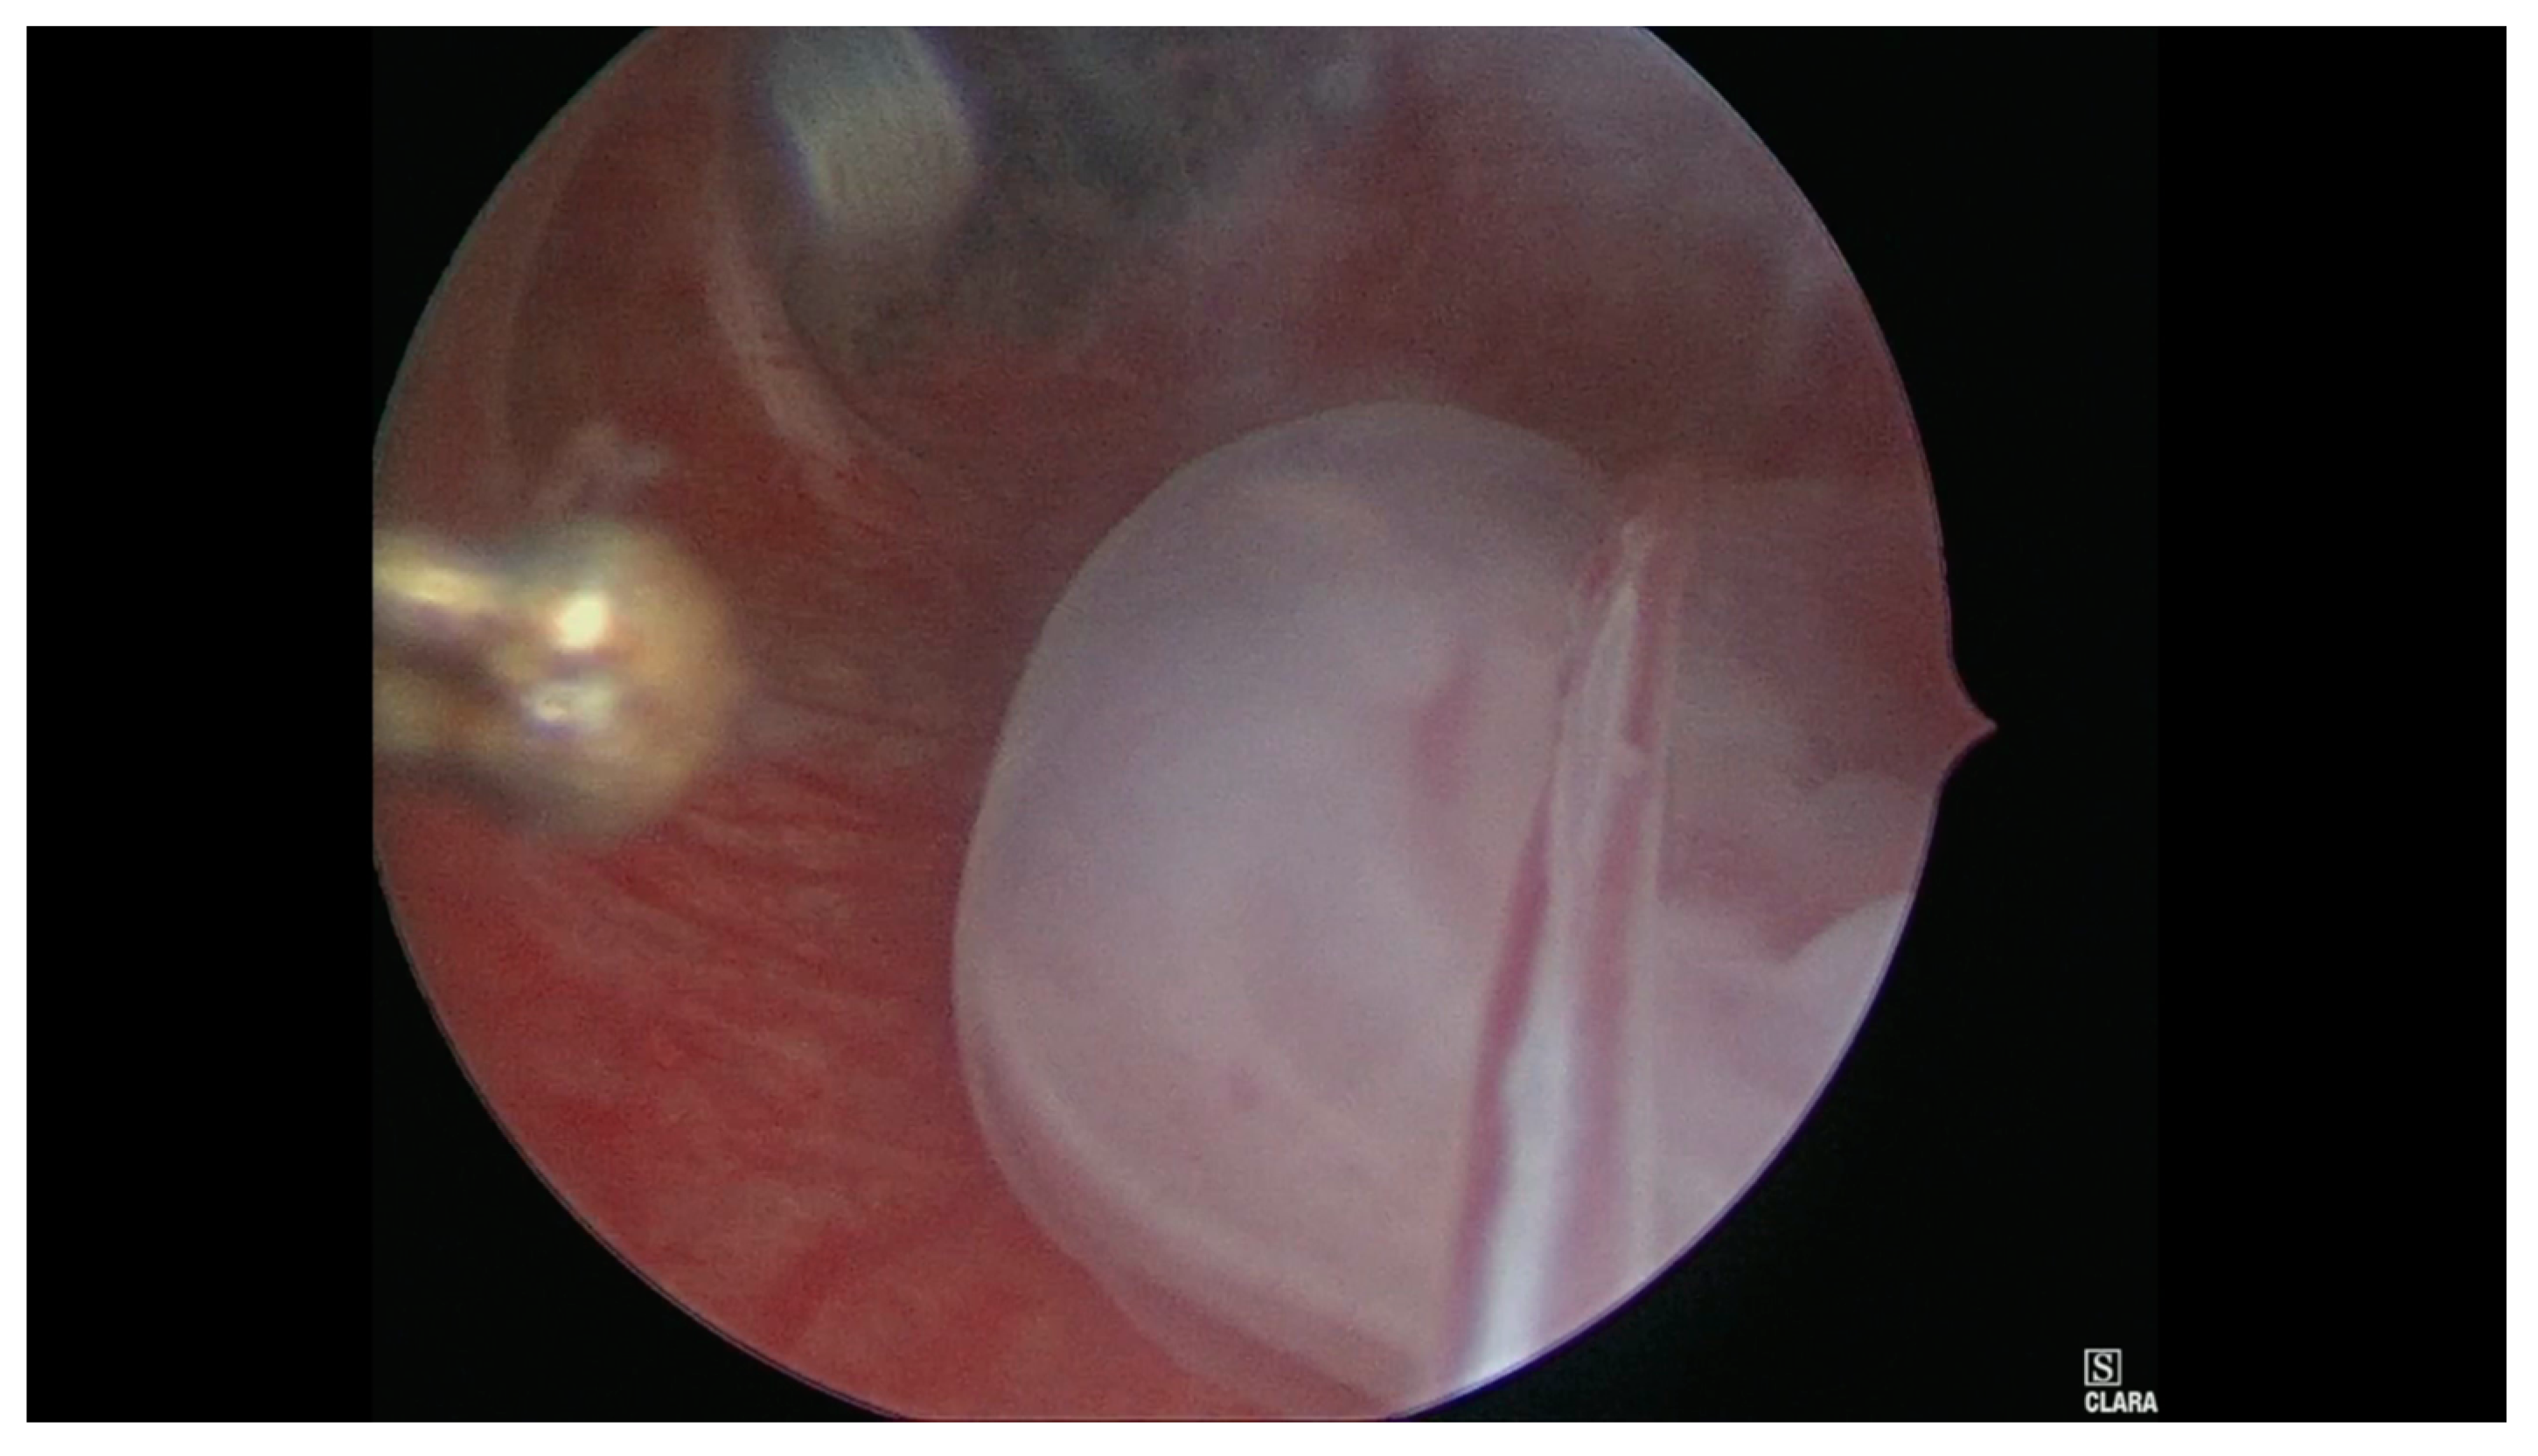

- Case 1. Hysteroscopy was performed in two steps. During the first phase a 5 mm Bettocchi hysteroscope (Storz®, Karl Storz SE & Co, Tuttlingen, Germany) with 5 Fr bipolar electrode Versapoint Twizzle (Gynecare®) was used to identify the GS: it was opened and the pregnancy terminated by cord section and vessels were partially coagulated; subsequently, the cervix was dilated and we performed a resectoscopy. During the second phase the GS and the embryo were removed and a 10 mm resectoscope with bipolar Versapoint (Gynecare®) was used to obtain a complete resection of the residual chorial villi. Lastly, we performed an electrocoagulation of the bleeding vessels on implantation site, in order to control the hemostasis (Figure 1, Figure 2, Figure 3 and Figure 4)